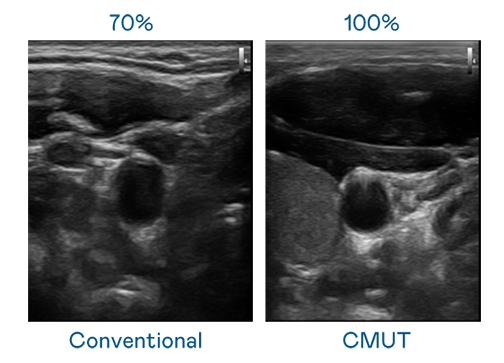

CMUT 技术是一种用电容式微机电元件来产生超音波讯号的技术。与传统 PZT 压电式技术相比,CMUT 频宽增加 30%,更宽频的超音波讯号让影像解析度大幅提升,是实现高影像品质医疗超音波扫描、促进精准医疗发展的关键技术。

超音波影像的解析度高低,首先取决于探头能发出的讯号频宽。亿万28 CMUT 可提供高清晰的超音波讯号,提供高频宽、高灵敏度、影像纹理细节更高的超音波影像,协助医护人员缩短影像判读时间及利用精准的医疗影像进行诊断。